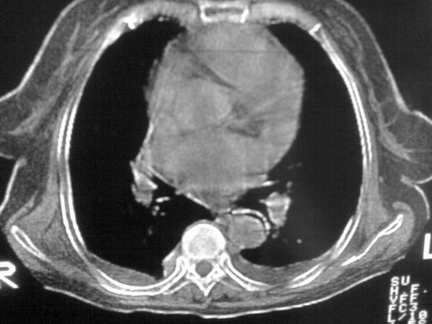

标题: CT13142:女 80 胸闷、气短、1w [打印本页]

标题: CT13142:女 80 胸闷、气短、1w

缩窄性心包炎

左室为主的心脏增大。

右肺感染;双侧胸腔少量积液,心影增大,可能与心功不全有关;胸内甲状腺肿。

右肺炎性变,双侧甲状腺肿,胸膜肥厚,心影增大考虑心功能不全.

胸内甲状腺肿;右肺中叶感染;双侧胸腔少量积液;心影增大,考虑有心功能不全。